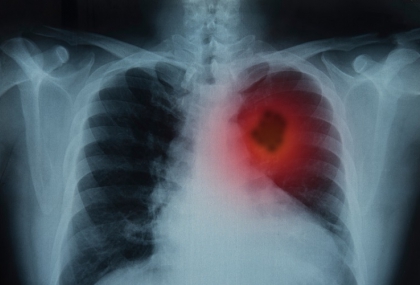

肺癌初期的症狀通常並不明顯,若出現胸悶、胸痛、超過兩周的持續咳嗽、咳嗽帶血絲、聲音沙啞、食慾不振,可能是肺部異常警訊,都該多加留意並及早就醫檢查。

肺癌早期不痛不癢! 醫點名「7大警示症狀」:聲音沙啞要當心

根據世界衞生組織(WHO)和國際癌症研究機構(IARC)的數據,肺癌是全球癌症死亡的主要原因。2020年,肺癌導致約180萬人死亡,占癌症總死亡數的18%。